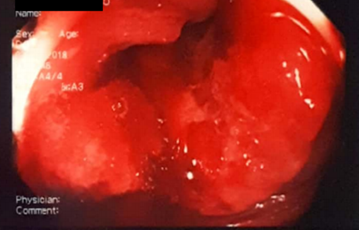

Patient, 56, female, previously healthy, underwent colonoscopy for malignancy research after occult blood in the stool positive. During the test it was observed findings suggestive of cancer, which was confirmed after biopsy-proven adenocarcinoma of the colon, and infiltrating ulcerated (Figure 1). Subsequently, the patient underwent rectosigmoidectomy performed by laparoscopy, with no significant complications during surgery. The pathological performed from surgical specimens demonstrated the presence of well-differentiated adenocarcinoma, ulceroinfltrativo type, measuring 3.6 cm in maximum extension without macroscopic perforations (pathological staging: pT2, pN0, PMX). During follow-up performed after surgery, oncology team conducted clinical follow-up and evaluation of the need for adjuvant therapy that was discarded due to the staging. A few months after the patient complained of weight loss and loss of appetite, which led investigation of recurrence or metastasis. Computed tomography was requested (CT) of the chest, abdomen and pelvis, which was observed only expansion of the colon loops in the area of colonic anastomosis and the presence of lymph nodes located in adjacent fat anastomosis enhanced due to the contrast, but with results inconclusive. Images of the chest and abdomen showed no changes.

Figure 1 Colonoscopy images depicting ulceroinfiltrative, vegetative lesion with friable surface, located in the sigmoid about 20 cm from the anal verge.